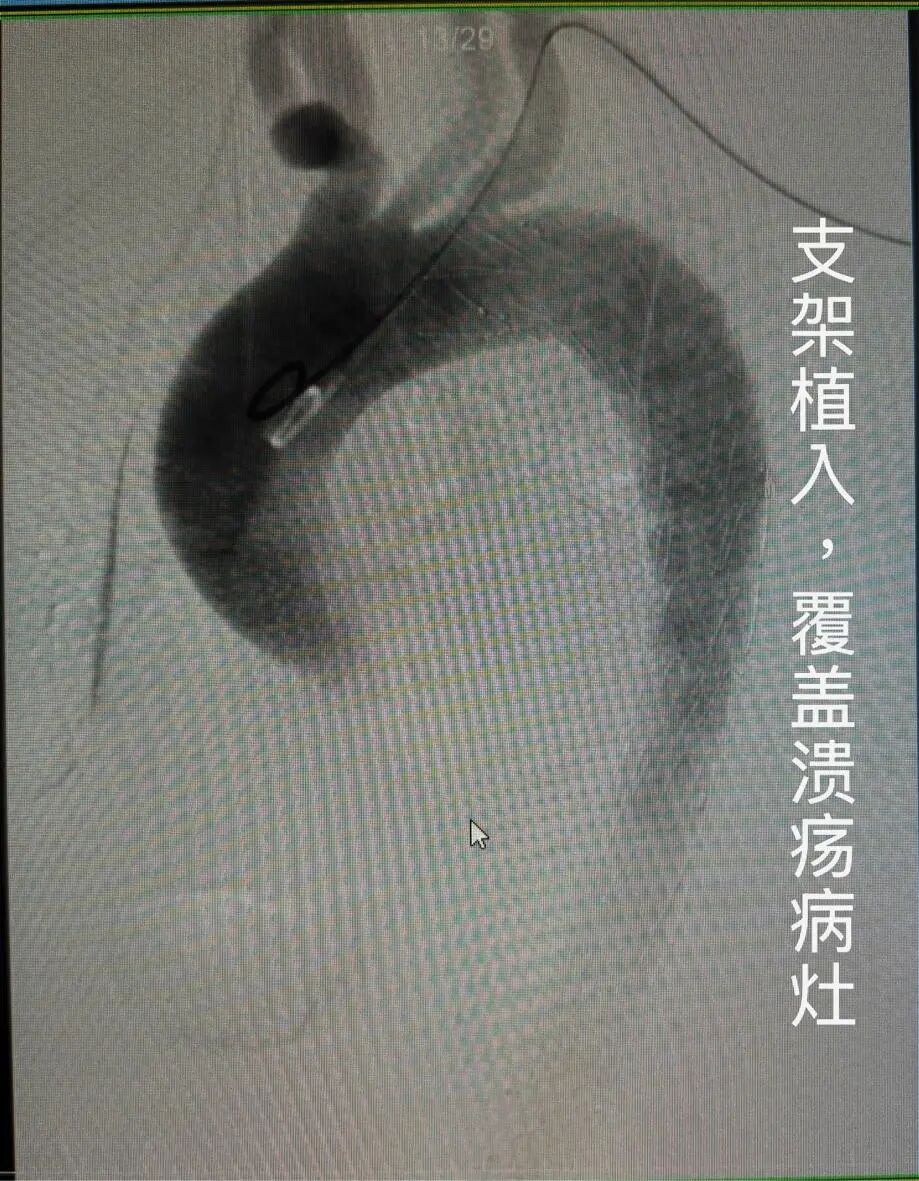

团队通过股动脉穿刺,将覆膜支架沿血管送至病变部位,精准释放后,支架像给血管“穿上”一层坚固“防护衣”,成功隔绝主动脉溃疡、封堵壁间血肿,从根源上避免了夹层形成与血管破裂的致命风险。

图:术后主动脉造影,可见网状支架完美贴附血管壁,主动脉管腔恢复通畅,病变被完全隔绝。